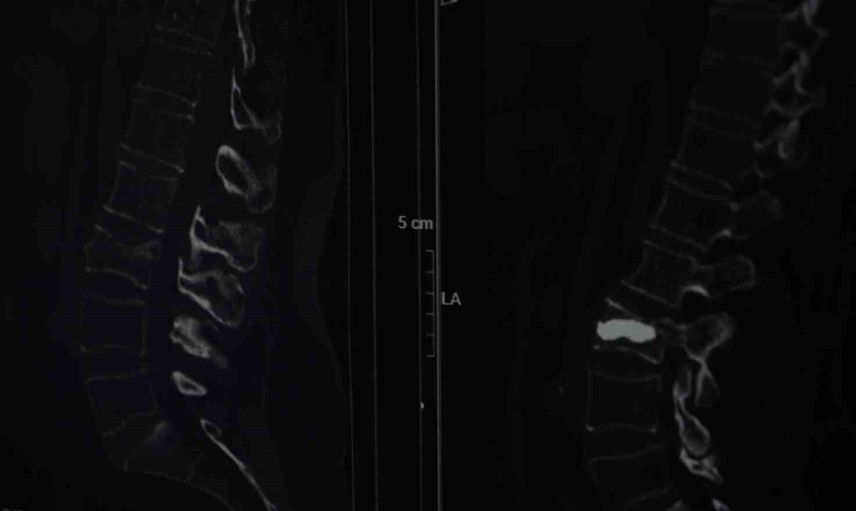

Ağrılar geçmeyince Şişli Hamidiye Etfal Eğitim ve Araştırma Hastanesi'ne başvurdu. Beyin ve Sinir Cerrahisi Uzmanı Doç. Dr. Şevket Evran ve ekibinin incelemelerinde, düşmeye bağlı olarak kemik erimesine bağlı bir omurga kırığı tespit edildi. Hastaya minimal invaziv yöntemlerle uygulanan kifoplasti 25 Ağustos günü gerçekleştirildi ve operasyon başarılı oldu.

Tedavi yöntemleri hakkında Evran, "Hastanın klinik durumu uygunsa vertebroplasti veya kifoplasti dediğimiz halk arasında omurgaya çimento doldurma olarak bilinen işlemi bu hasta grubunda uygulamak öncelikli tercihimiz oluyor" dedi ve uygulamanın avantajlarını anlattı. Evran, uygulama tekniğini şu sözlerle açıkladı: "Vertebroplastide hastanın cildinde büyük bir kesi olmadan sadece bir iğnenin geçtiği kadar bir delikten iğne yardımıyla girilerek omurganın içine bazen tek bazen çift taraflı girilerek başlangıçta içinde sıvı olan sonra katılaşan bir maddeyi enjekte ediyoruz. Omuriliğin içinde donuyor. Başka bir yöntemi olarak da bazen omurganın içinde bir balon yardımıyla balon şişirerek omurganın eski yüksekliğini kazanmasına ve daha güvenli bir alan oluşturarak balonun şiştiği alana çimento dediğimiz şeyle doldurarak hastanın da ağrılarının geçmesini sağlamış oluyoruz, akşamına hasta taburcu edilebiliyor."